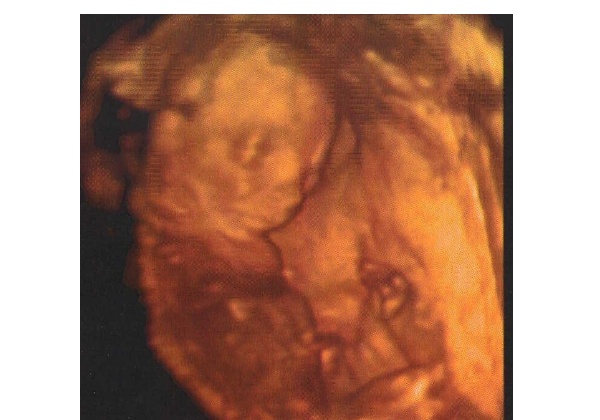

De minden rendben van. Az előző uhu az bénauhugép volt. Viszont a mostani szuper volt, megint átkapcsolgatott 4d-re. Most nem ettem csokit előtte, de nem is volt annyira ficánka. De azért mozgolódott, nem nagyon állt meg, csak nem akkora lendülettel, mint ez előtt. Lehet, hogy már nincs annyi helye, mint a 12. héten, amikor még bukfencezgetett. Meg kell enni, olyan édeske. Már van rajta egy kis husi is, nem olyan csonti. Az arcocskája meg teljesen látható volt. Akkora 4d kukit láttunk, hogy anyu elpityeregte magát… A vizsgálat alatt majd be pisiltem, mire mutatta a doki, hogy látom-e, épp a hólyagomat rugdossa. Mondtam, hogy érzem én azt